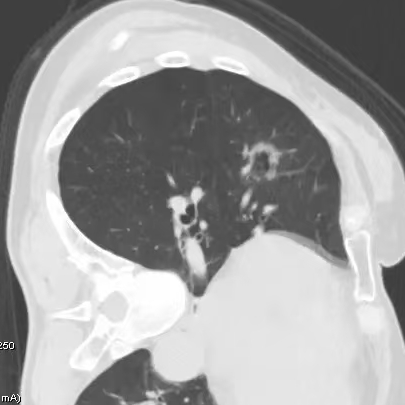

健康直通车: 健康是生命的宝贵财富,也是幸福生活的基石。为了更好地服务广大百姓,传播健康知识,葫芦岛市第二人民医院推出“健康直通车”专题栏目,将专业的医学知识以通俗易懂的方式传递给每一位市民,掌握科学的疾病预防方法,共同构筑健康中国的坚实基石。 什么是肺结节 肺结节是指肺内直径小于或等于3cm的类圆形或不规则形病灶,影像学表现为密度增高的阴影。大于3cm的称肿块。肺结节依其密度不同可分为实性结节、部分实性结节、磨玻璃结节,其中部分实性结节的恶性可能性最大,磨玻璃结节次之,实性结节尤其是小的实性结节结节最可能是良性的。 肺结节的常见病因 1、良性(约90%) 🔸 感染:结核、真菌、细菌性肺炎后遗留的瘢痕; 🔸 非感染:错构瘤(良性肿瘤)、炎性假瘤、血管瘤等。 2、恶性(约10%) 🔸原发性肺癌(如腺癌、鳞癌); 🔸转移性肿瘤(其他器官癌症转移至肺)。 如何根据影像判断肺结节性质 1、依据结节大小判断 🔸小于0.5cm的肺结节绝大多数都是良性的,属于微小结节。即使部分小于0.5cm肺结节是恶性的,但是适当的观察不影响预后。每年复查一次胸部CT就可以。 🔸大于0.5cm持续存在的纯磨玻璃结节,观察6个月,若持续存在,不管有无进展均多数是恶性的,视患者意愿,手术可以立即做也可观察至进展再做,不影响预后。 🔸大于0.8cm的部分实性结节恶性可能性非常大,应积极评估结节边缘毛刺、分叶、胸膜凹陷等征象。 🔸若实性部分大于0.5cm,恶性率显著提高。若在3~6个月随访期间实性部分增大或者总体部分增大,都可以考虑手术切除。而即使小于0.8cm的部分实性结节也需3个月就复查对比。 2、依据肺结节形态 如CT上提示病灶形态不规则、毛刺、分叶、胸膜凹陷、空泡征、血管集束征等,符合恶性肿瘤的征象。 🔸结节与正常肺组织之间界限非常清楚的恶性可能性大。 🔸结节密度不均呈混杂密度或均匀较大纯磨玻璃结节也基本是恶性的。 🔸有胸膜牵拉(不管是肺表面的脏层胸膜还是叶间裂部位的胸膜)的恶性可能性大。 🔸结节有浅分叶、细毛刺,密度较高而与周围肺组织边界不清的恶性可能性大。 🔸磨玻璃或混合磨玻璃结节存在小空洞的恶性可能性大。 🔸影像上似慢性炎表现,而没有炎症相关的其他异常,特别当所谓炎症区域内部或一侧与正常肺组织之间界限非常清楚的基本上是恶性的。 3、从结节发展情况来看 所有随访中增大进展的都需要考虑恶性可能,不进展而持续存在的纯磨玻璃结节也需考虑恶性。 葫芦岛市第二人民医院肺结节诊治中心孙振教授深耕肺结节领域四十余载,凭借对临床实践的执着钻研与深厚积淀,在肺结节精准诊断及鉴别诊断领域形成独到见解。他系统总结海量临床病例,创新性提炼出一套科学化、规范化的肺结节全周期诊疗体系,尤其在早期微小结节的影像特征识别、良恶性风险分层等方面积累了丰富经验,为众多患者提供了精准、高效的诊疗方案。 人民医院·人民名医 孙振 主任医师 三级教授 ·葫芦岛市第二人民医院胸外科主任、肺结节诊治中心主任 ·中国医科大学客座教授 ·原央企总医院著名胸外科专家 ·辽宁省医学会胸外科委员 ·辽宁省抗癌协会肺癌专业委员会委员 ·辽宁省细胞生物学学会食管癌专业委员会理事 ·主持多项科研成果获科技成果奖、科技进步奖、国家专科奖项 医学成就 从事胸外科临床工作近40年,担任胸外科首席专家及科室主任20余年,是我省胸外科领军人物,推动肺癌、食管癌等胸部肿瘤外科的规范化诊疗,在央企总医院牵头成立了肺结节诊疗中心,率先开展CT引导下肺内小结节定位切除,既确切完整切除肺内小结节,又降低肺功能损害。 专业特色 擅长肺癌、食管癌的外科手术和综合治疗,在各类高难度胸外伤手术治疗、胸腔镜微创手术、胸腺瘤手术及复杂并发症处理方面具有高深造诣,尤其擅长肺癌早期诊断,胸部小结节CT早期肺癌的鉴别等。完成各类高难度胸外科手术5000余例,其中微创手术占比达90%,治愈率达98%,多项业务填补省内空白。 开展的高难手术 胸腔镜肺部结节微创手术、肺癌根治术、食管癌根治术、各种纵隔肿瘤切除术、胸骨后甲状腺手术及胸部复合性外伤的抢救手术等。